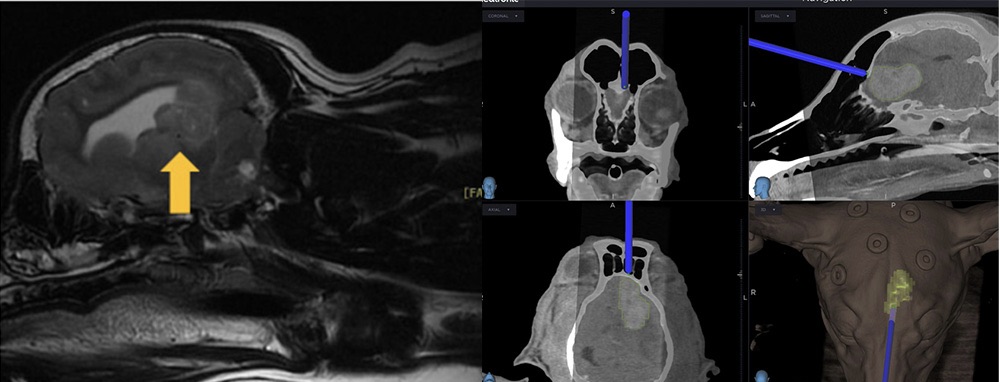

브레인 네비게이터

CT·MRI 기반 3D 재구성과 실시간 위치 확인으로 반려동물 뇌수술의 정확성과 안전성을 높이는 영상 유도 수술 시스템입니다.

수술 전에는 뇌 구조를 3차원으로 재구성해 접근 경로를 계획하고, 수술 중에는 병변 위치와 경로를 확인하며 보다 정밀한 접근을 지원합니다.

브레인 네비게이터 장비 사진

수술 중 브레인 네비게이션 화면